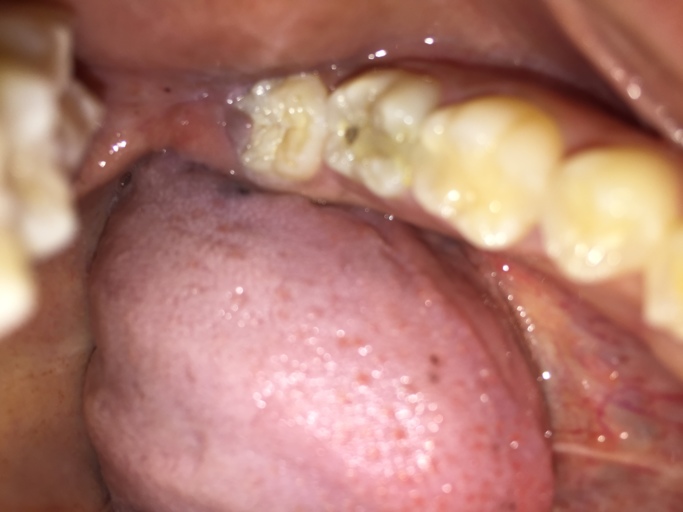

Is this a cavity in my wisdom tooth?

Hi, I am 31 and have observed a dark spot on my lower wisdom tooth (the tooth behind the one with the large silver filling on the picture). All my wisdom teeth have erupted quite good, but short after eruption I had small cavities which were filled...